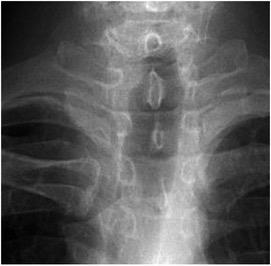

Paciente con cánula de traquestomía y fosa supraclavicular visible

Ominsky S et al. The Suprasternal Fossa. Radiology 1977

Paciente con traqueostomía previa. Estenosis relativa en el área de la cirugía. Fosa supraesternal visible.